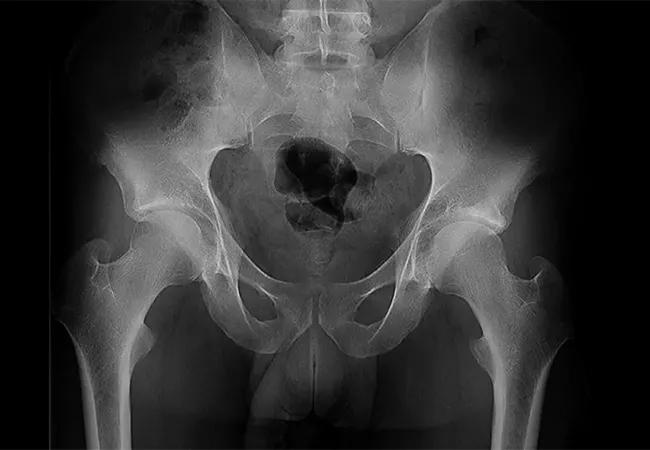

A 21-year-old male presented to Cleveland Clinic’s Center for Hip Preservation for treatment of symptomatic left hip pain, which developed over time in his occupation as a heavy manual laborer.

The patient’s physician, Atul Kamath, MD, who is also director of the center and staff surgeon in the Orthopaedic and Rheumatologic Institute, notes that anteroposterior imaging showed that the patient was skeletally mature. And while the cartilage on his left hip was preserved, Dr. Kamath also noticed a crossover sign, indicating acetabular retroversion, a posterior malorientation of the acetabulum. Acetabular retroversion can predispose patients to femoroacetabular impingement and is a risk factor for early-onset osteoarthritis of the hip.

Dr. Kamath chose to address the complex deformity with introverting, or reverse PAO (anteverting periacetabular osteotomy), where the shape of the socket is manipulated to create more effective anteversion and dramatically increase range of motion. “This offers a powerful method for treating the impingement within the hip, and then also affording more normal biomechanics given the anteverted socket,” he says.

Dr. Kamath notes that postoperative imaging demonstrates elimination of crossover sign and fixation through the PAO. The patient is doing well and was able to return to his work with great functional improvements and decreased pain.